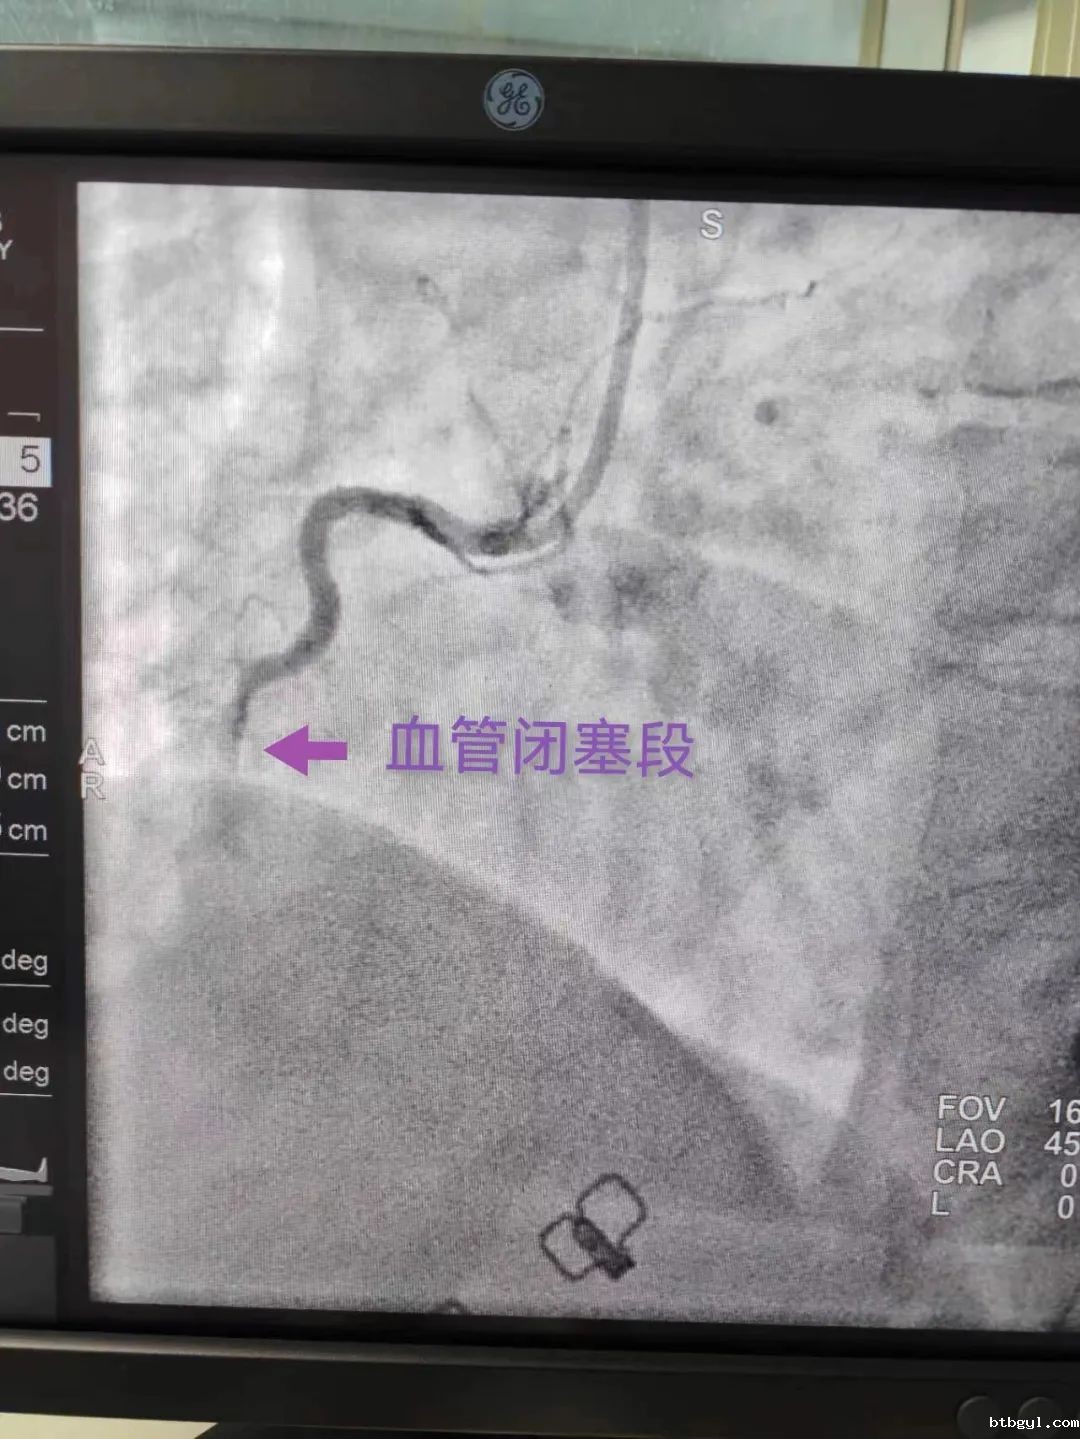

“合江县胸痛中心群”发来信息 胸痛中心协调员迅速回应 11月29日下午4点57分,“合江县胸痛中心群”对话框显示出院前急救医生罗会发出的心电图,并提供简要病史:患者53岁女性患者,有高血压病史,胸痛半小时,心电图提示急性下壁ST段抬高型心肌梗死,目前血压偏低,距离到达医院10分钟车程。 消息立即引起胸痛值班人员的关注,情况危急,患者随时有生命危险!胸痛中心协调员谢勇及医疗总监张永强立即做出回应:患者诊断明确,有行急诊冠脉造影及PCI指征,建议双绕直接送导管室,先负荷双抗药物,预谈话,完善术前准备。 急救车内车外信息共享 各岗位医护人员各司其职 张永强主任通过微信群与随车罗会医生保持沟通和联络,并指导罗会医生,在急救车上尽可能与患者及家属充分沟通病情,如果同意急诊介入手术,可以考虑绕行急诊科、CCU,直接到达导管室。 罗会医生告诉患者随时有突发心血管恶性事件可能,尽早开通血管,才能救活更多心肌,挽救患者生命!时间就是心肌、时间就是生命!目前最快最直接的方法就是器械开通,我院心内科介入团队有充足的能力开通病变血管。 16:58 患者家属口头同意介入手术(17:11签字确认),院前护师给患者顿服阿司匹林300毫克及氯吡格雷300毫克。 16:59张永强主任启动导管室。 CCU病房预留床位、导管室提前激活、心内科手术医生提前到位,接诊工作在患者到达之前全部准备就绪。 17:10 120车驶进医院大门 双绕直达导管室; 17:15谢勇主治医师消毒铺巾并桡动脉穿刺; 17:16 桡动脉穿刺成功并给予肝素抗凝; 17:18开始冠状动脉造影检查。 造影发现,患者优势右冠脉中段闭塞,病情凶险!但术者凭借丰富的手术经验及娴熟的操作技术,根据具体情况制定出对应的手术方案。很快,导管成功到位右冠开口。 17:26经过重重阻碍,导丝终于顺利通过闭塞段到达右冠远端真腔,阻塞的血管重现了血流! 至此,心血管团队创造了心梗患者救治的“奇迹”,D-TO-W时间仅16分钟,这是必威betway西汉姆联官方网站胸痛中心至今的最佳成绩!(之前最佳是双绕急诊PCI,D-TO-W时间23分钟),手术顺利完成,手术医生及护士携带除颤仪将患者护送至CCU。 必威betway西汉姆联官方网站党委书记、胸痛中心主任陈应军在肯定成绩的同时,作了三点要求: 1、急救战线前移,打通胸痛救治最后一公里,让更多高危胸痛病人得到及时的救治; 2、时间就是心肌,时间就是生命。提高双绕比例,缩短D-W时间至60分钟之内,提高救治成功率。 3、继续通过医患微信群、现场义诊、宣教等方式加强民众对胸痛知识的认知度,缩短胸痛发病至就诊时间,降低急性心肌梗死的发病率及死亡率。 这次救治中D-TO-W 16分钟的新突破充分展示了我院胸痛中心过硬的心梗救治能力,同时,也反映了我院胸痛中心在整个合江地区胸痛中心建设推进过程当中的显著成效。 必威betway西汉姆联官方网站是合江地区唯一能全天24小时行急诊PCI的医疗单位。 在院领导班子的正确带领下,胸痛中心运行近两年来取得了长足的进步。随着胸痛中心的建设,各重点科室业务能力得到了提升,心血管介入水平明显提升,救治的危重患者较前增加,死亡率下降。目前今年行急诊PCI近80例,胸痛中心在每位医护人员的共同努力下,2023年行PCI超300例,技术力量及救治水平的不断提高将造福更多的胸痛患者。 在胸痛中心建设的路上我们任重而道远,在前进的道路上必威betway西汉姆联官方网站胸痛中心勠力同心、履职尽责、勇于担当,为合江县人民的健康保驾护航!